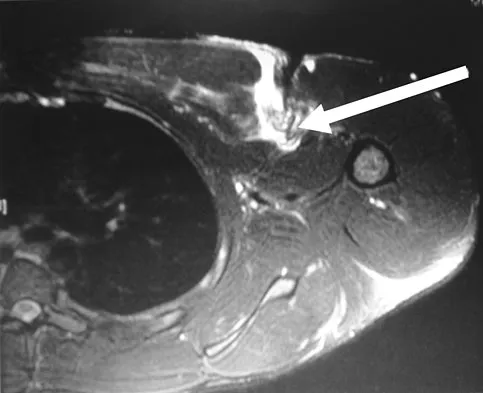

Figure 37 shows the T2-weighted MRI scan of the hip joint. What structure is labeled A?

Explanation